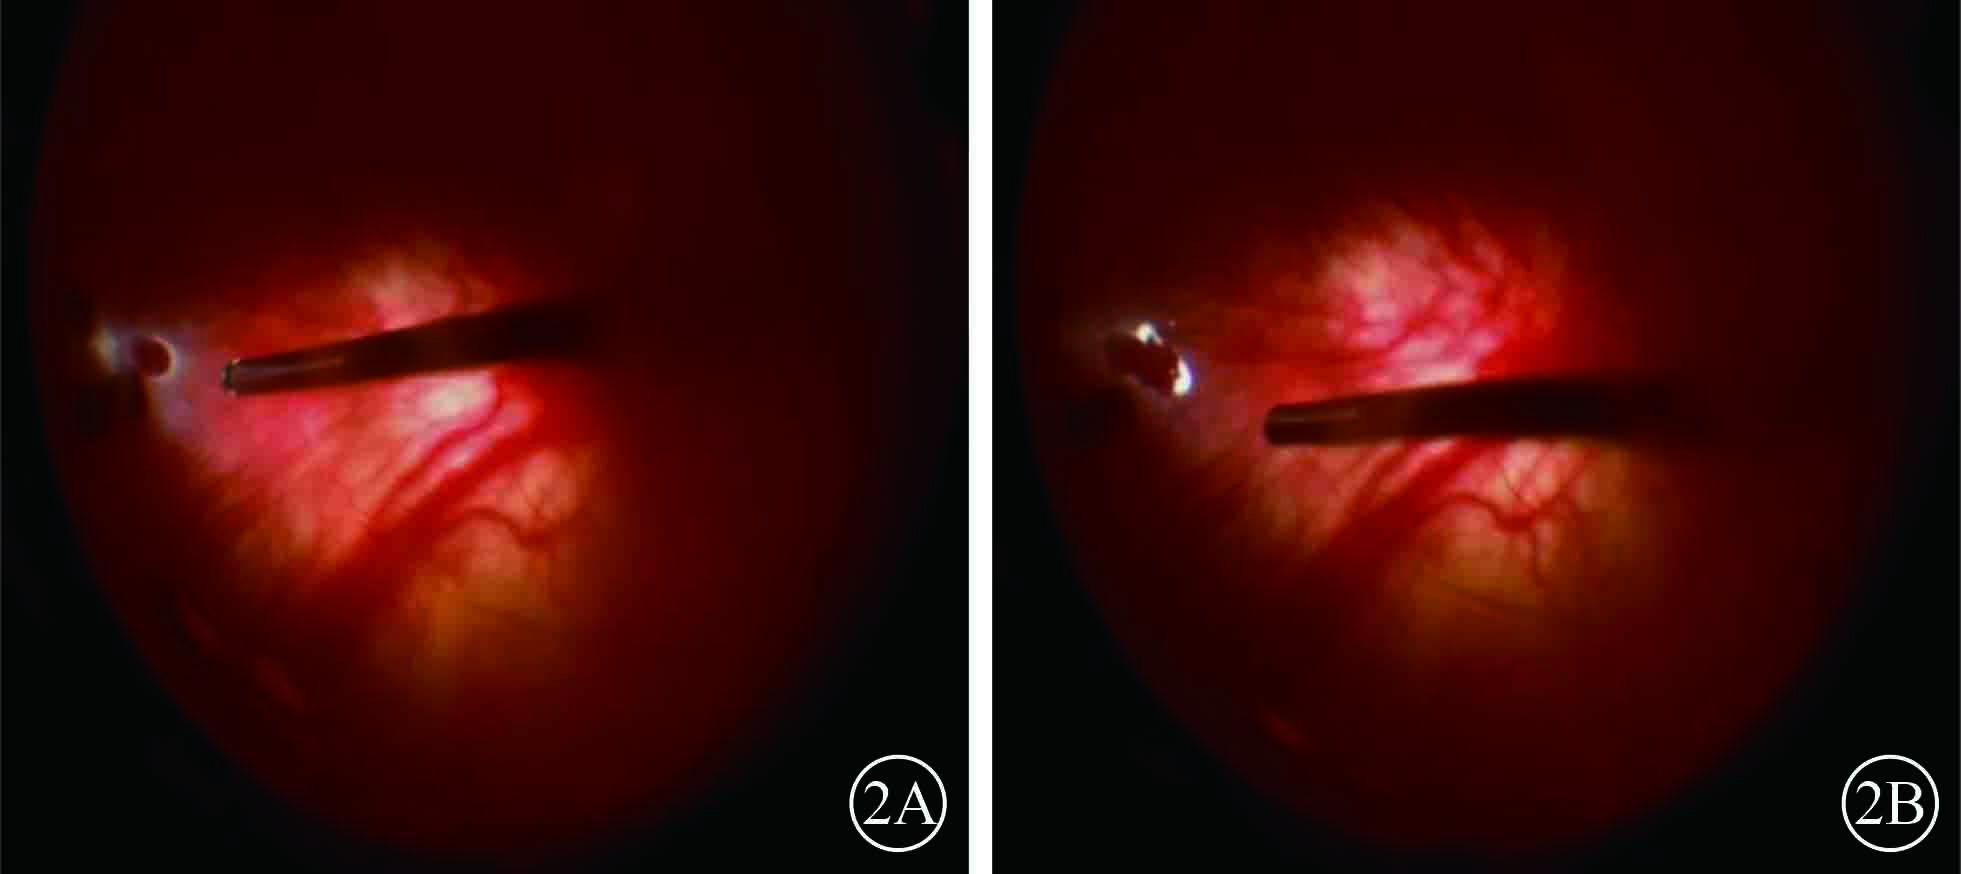

患者男,35歲。因體檢發現雙眼視網膜脫離1月余于2015年3月12日來我院眼科就診。患者自幼皮膚、毛發、虹膜無色素;雙眼視力差、畏光。否認外傷史、家族史。眼部檢查:右眼視力數指/30 cm,左眼視力0.1;雙眼矯正視力均無提高。雙眼眼瞼皮膚及睫毛均無色素;眼球水平震顫;角膜透明,瞳孔圓,虹膜半透明;晶狀體透明。雙眼眼底呈橙色。右眼全視網膜脫離,左眼0~8點時鐘位視網膜脫離(圖1);雙眼視網膜裂孔均窺不清。A型超聲檢查,右眼、左眼眼軸長度分別為26、28 mm。診斷:(1)雙眼孔源性視網膜脫離(疑似);(2)雙眼高度近視;(3)眼皮膚白化病。分別于2015年3月23日、5月11日行左眼、右眼視網膜復位手術。采用標準25G經睫狀體平坦部玻璃體切割手術。手術中見左眼視網膜裂孔分別位于 1、2、4、6點時鐘位,右眼裂孔位于8、11點時鐘位。先采用眼內電凝對裂孔邊緣進行標記,電凝處理后裂孔邊緣呈白色外觀(圖2);視網膜復位后,采用視網膜冷凍替代常規激光光凝對裂孔進行封閉;最后進行硅油眼內填充。雙眼均于手術后3個月行硅油取出手術。硅油取出后3個月,雙眼視網膜復位良好,眼底呈橙色,透見脈絡膜大血管(圖3);6個月,右眼視網膜復位良好,左眼下方視網膜再次脫離。于2016年2月1日再次行左眼視網膜復位手術、硅油填充。2016年12月27日隨訪,右眼視網膜復位良好;左眼硅油填充,下方視網膜仍有局部脫離(圖4)。

右眼手術中視頻剪輯像。2A. 8點時鐘位周邊視網膜圓形裂孔;2B. 電凝后視網膜裂孔邊緣呈白色外觀

右眼手術中視頻剪輯像。2A. 8點時鐘位周邊視網膜圓形裂孔;2B. 電凝后視網膜裂孔邊緣呈白色外觀

患者男,35歲。因體檢發現雙眼視網膜脫離1月余于2015年3月12日來我院眼科就診。患者自幼皮膚、毛發、虹膜無色素;雙眼視力差、畏光。否認外傷史、家族史。眼部檢查:右眼視力數指/30 cm,左眼視力0.1;雙眼矯正視力均無提高。雙眼眼瞼皮膚及睫毛均無色素;眼球水平震顫;角膜透明,瞳孔圓,虹膜半透明;晶狀體透明。雙眼眼底呈橙色。右眼全視網膜脫離,左眼0~8點時鐘位視網膜脫離(圖1);雙眼視網膜裂孔均窺不清。A型超聲檢查,右眼、左眼眼軸長度分別為26、28 mm。診斷:(1)雙眼孔源性視網膜脫離(疑似);(2)雙眼高度近視;(3)眼皮膚白化病。分別于2015年3月23日、5月11日行左眼、右眼視網膜復位手術。采用標準25G經睫狀體平坦部玻璃體切割手術。手術中見左眼視網膜裂孔分別位于 1、2、4、6點時鐘位,右眼裂孔位于8、11點時鐘位。先采用眼內電凝對裂孔邊緣進行標記,電凝處理后裂孔邊緣呈白色外觀(圖2);視網膜復位后,采用視網膜冷凍替代常規激光光凝對裂孔進行封閉;最后進行硅油眼內填充。雙眼均于手術后3個月行硅油取出手術。硅油取出后3個月,雙眼視網膜復位良好,眼底呈橙色,透見脈絡膜大血管(圖3);6個月,右眼視網膜復位良好,左眼下方視網膜再次脫離。于2016年2月1日再次行左眼視網膜復位手術、硅油填充。2016年12月27日隨訪,右眼視網膜復位良好;左眼硅油填充,下方視網膜仍有局部脫離(圖4)。

右眼手術中視頻剪輯像。2A. 8點時鐘位周邊視網膜圓形裂孔;2B. 電凝后視網膜裂孔邊緣呈白色外觀

右眼手術中視頻剪輯像。2A. 8點時鐘位周邊視網膜圓形裂孔;2B. 電凝后視網膜裂孔邊緣呈白色外觀